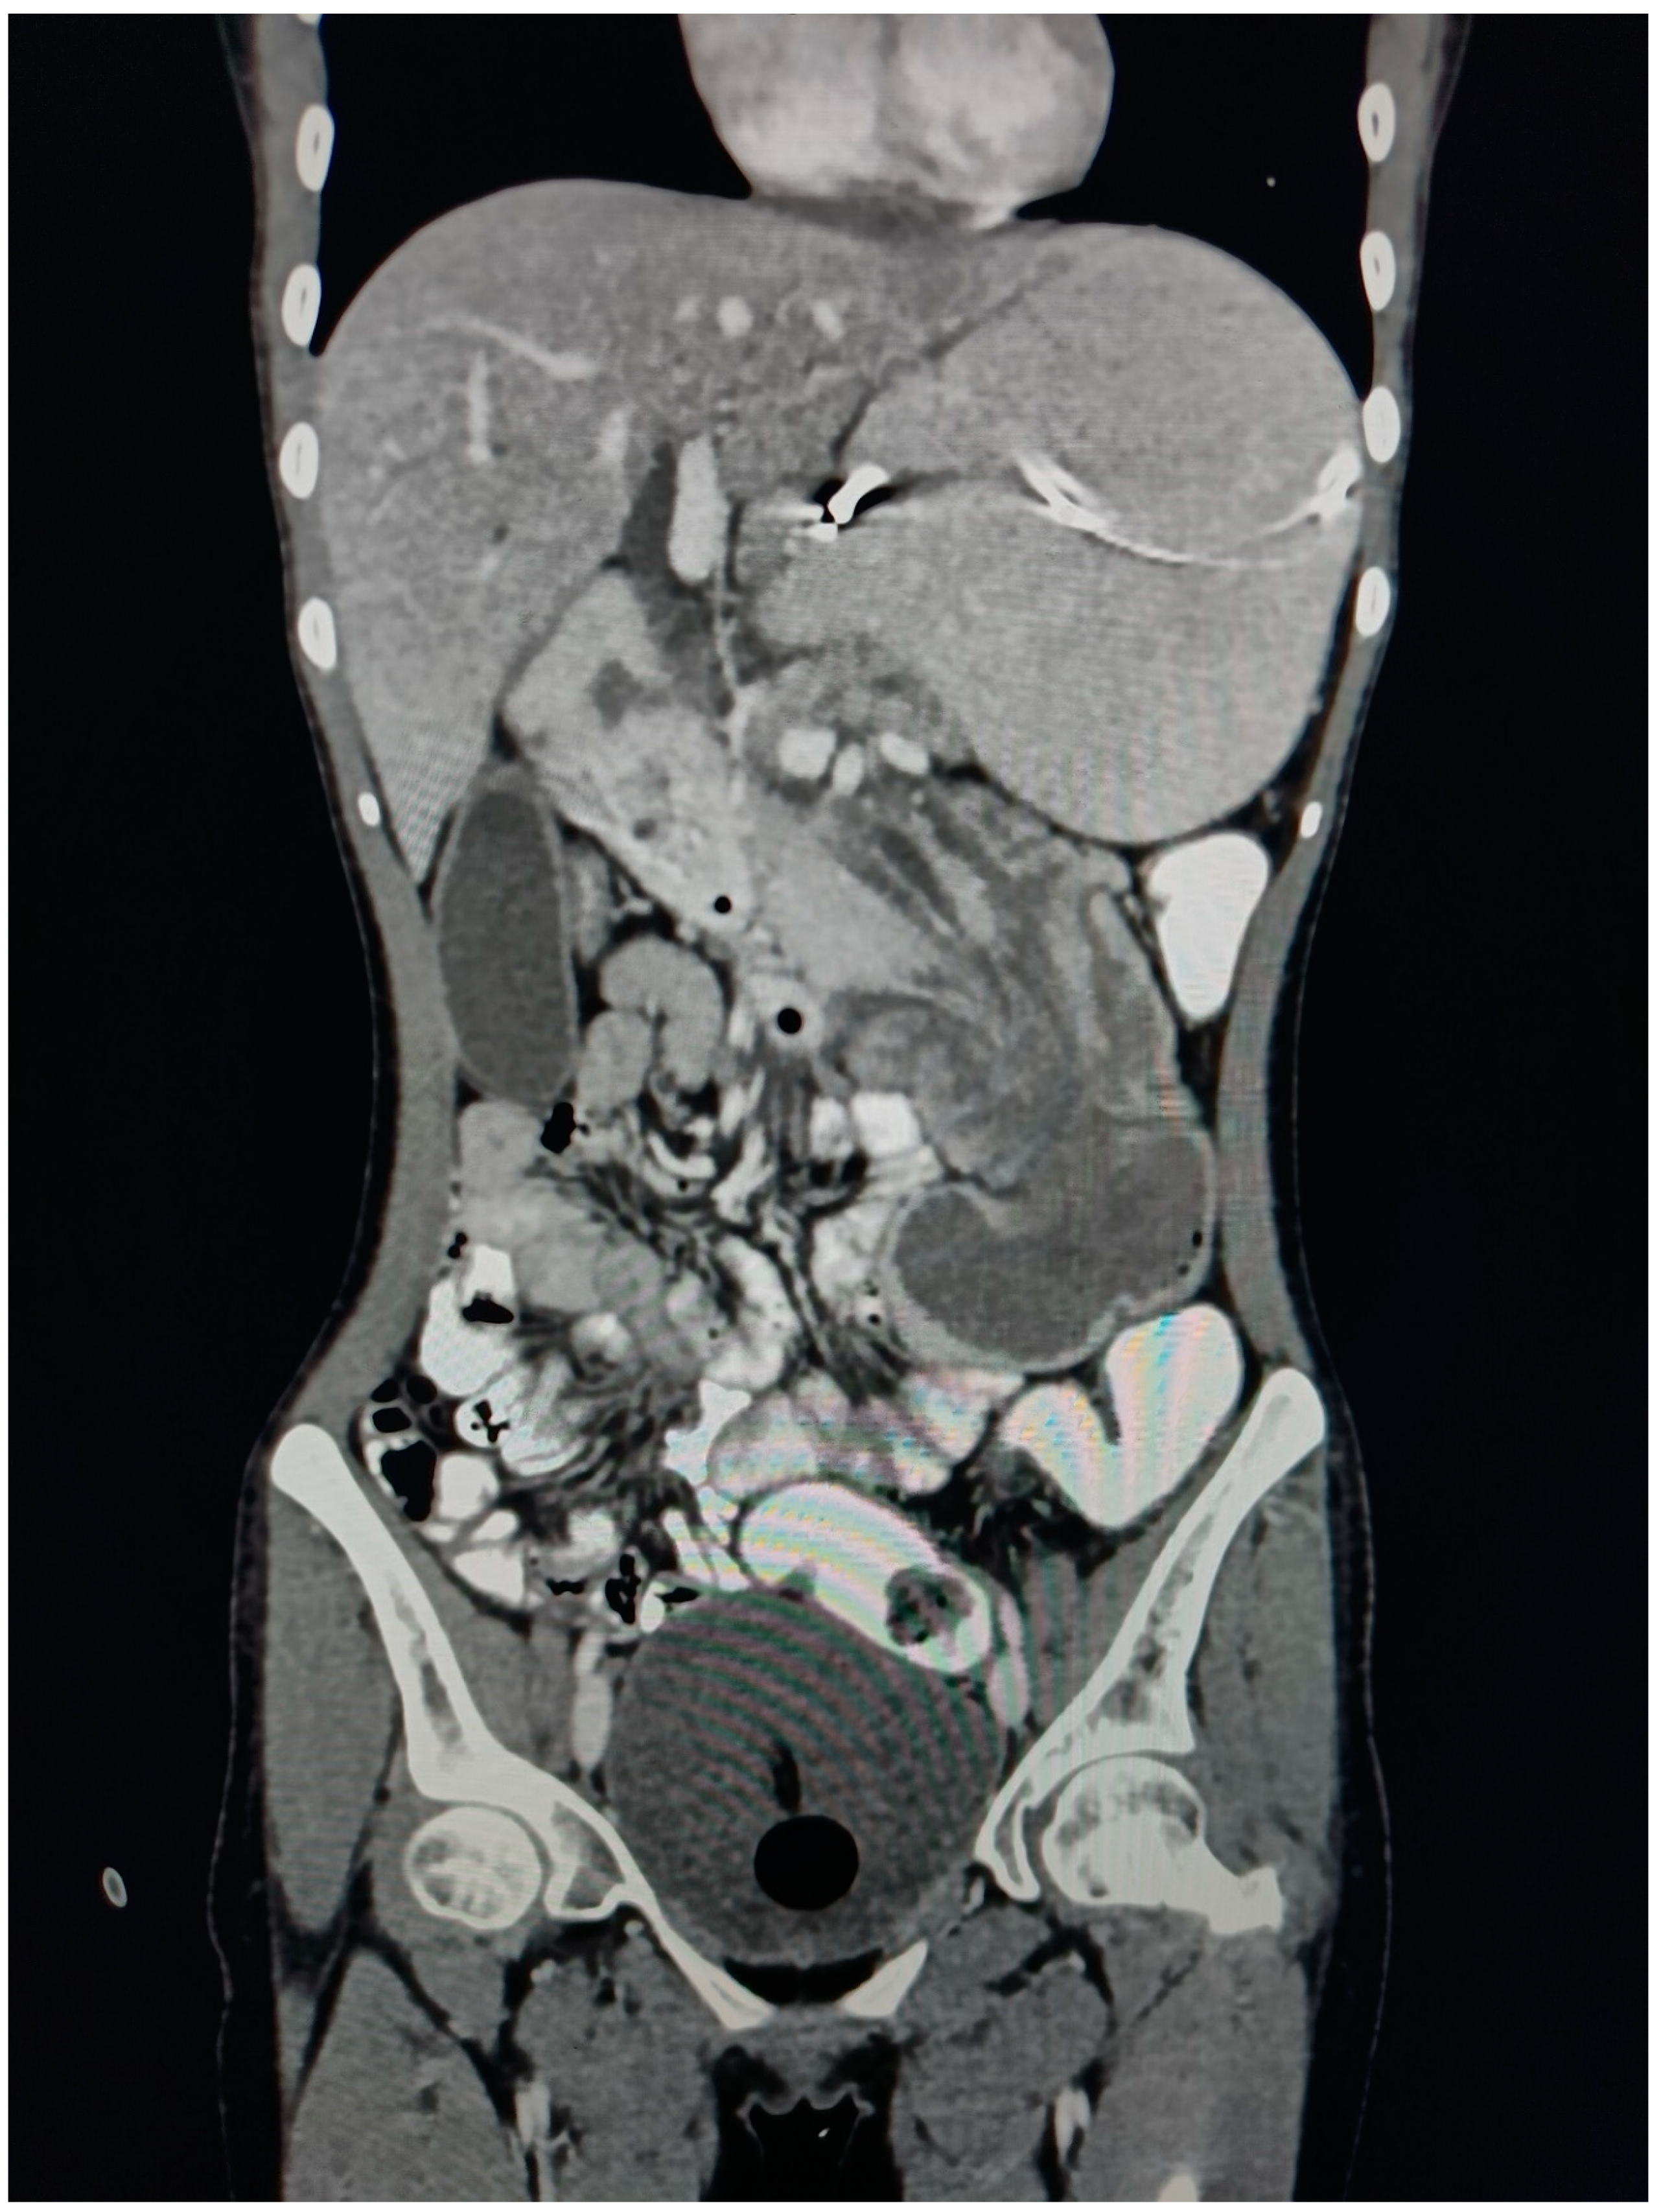

Figure 1. CECT Axial Abdomen showing Bowel within bowel appearance giving TARGET/ DOUNUT sign.

On CECT examination, there is evidence of long segmental intussusception noted at the level of the distal 2nd part of the duodenum with resultant proximal dilated proximal duodenum and stomach. These findings are compatible with the duodenal-duodenal type of enteroenteric intussusception.

The Intussusceptum is 2nd part of the duodenum, the ampulla of the Vater, the head, and the uncinate process of the pancreas while the intussusipens is 3rd and 4th part of the duodenum. The content of the Intussusceptum shows homogenous post-contrast enhancement. The length of the Intussusceptum measures approximately 7 cm.

The Intussuscipens shows enhancing reactionary wall thickening of the 3rd and 4th part of the duodenum and proximal jejunum, maximum wall thickness measures approximately 8 mm of the 4th part of the duodenum. The Intussusceptum does not show any obvious mass lesion or lead point, however underlying ampullary lesion cannot be ruled out owing to the presence of a double duct sign.